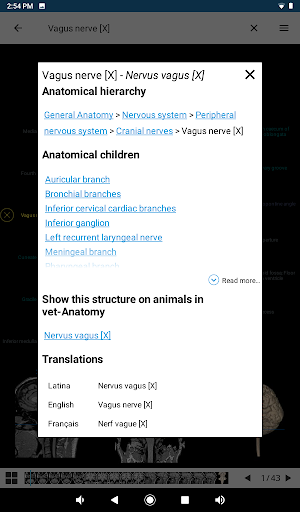

e-Anatomy memiliki lebih dari 26.000 gambar yang berisi serangkaian gambar dalam tampilan aksial, koronal, dan sagital serta radiografi, angiografi, gambar diseksi, bagan anatomi, dan ilustrasi. Semua gambar medis diberi label dengan cermat, lebih dari 967.000 label tersedia dalam 12 bahasa termasuk Terminologia Anatomica Latin.

- Ketuk label untuk menampilkan struktur anatomi

* Memperbaiki interaksi dengan hierarki anatomi

*Jelajahi bagian-bagian anatomi menggunakan tautan deskripsi